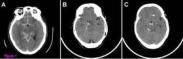

蛛網膜下腔出血